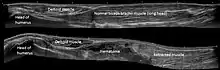

The split line between the long and short heads